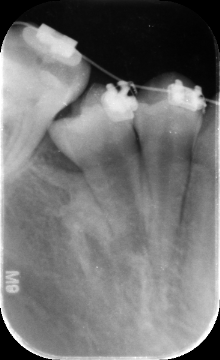

与外科合作后牵引1个月后的小牙片